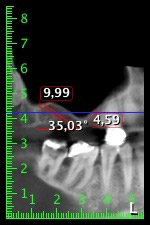

Die 59-jährige Patientin wurde mit einer fortgeschrittenen Parodontitis vorstellig, beschrieb ein ungutes Gefühl und einen schlechten Geschmack ausgehend vom ersten Quadranten distal. Die klinische Untersuchung zeigte allgemein erhöhte Taschentiefen und einen stark fortgeschrittenen Knochenabbau in regio 16 und 14. Die radiologische Untersuchung untermauerte den Befund (Abb. 1). Die Zähne 16 und 14 waren nicht zu erhalten.

Abb.1: Orthopantomogramm mit Knochenabbau in Regio 16–14.*